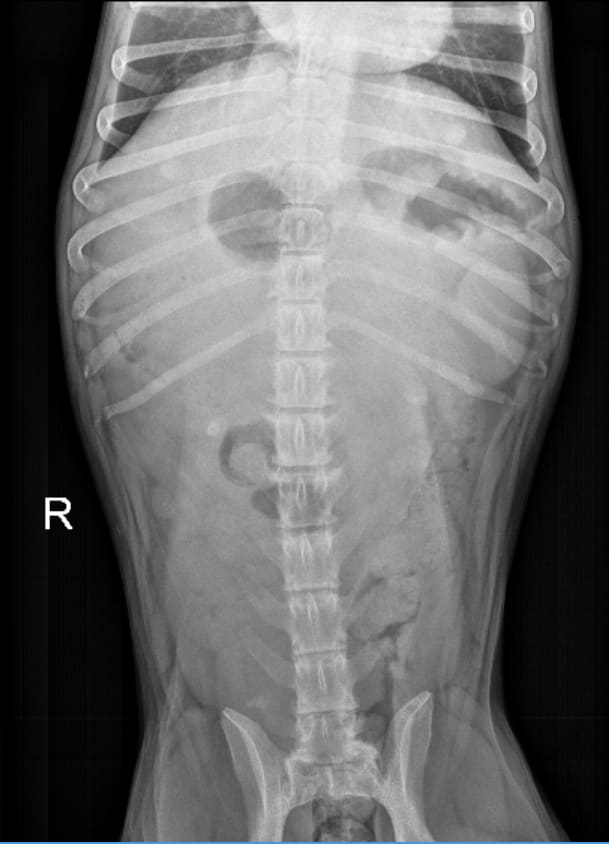

Hi, Ferg swallowed a piece of flat rubber ball about 1''x2.5'' a week ago. She has been asymptomatic. Xrays were taken and radiologist said there is no sign of foreign object. However, in the 1st pic, the outline seems to resemble the piece of rubber that was ingested. Is that the stomach? Am I overreacting? Also are there other anomalies shown on the Xray? Thank you for your time.

I see what you’ve circled in you picture but I think it looks more like a fold in the stomach, especially when you look at the other x-ray view. I would trust the radiologist - if Fergie starts to show symptoms of a gastric foreign body then you might want to have an ultrasound performed.